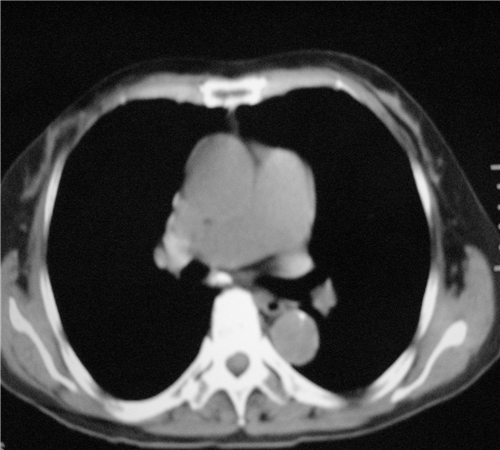

标题: CT26849:女67岁反复胸痛两天余,临床考虑夹层。 [打印本页]

标题: CT26849:女67岁反复胸痛两天余,临床考虑夹层。

右肺感染,未见夹层。

未见夹层

既然考虑夹层,建议强化!另:右下肺感染!

1)右肺感染性病变。2)建议行ct增强扫描或mri检查排除主动脉夹层。

双下肺感染,右侧显著。有无夹层,增强扫描后再诊断。

1. 感染性病变,2.未见夹层,3.食道未见异常。

平扫未见确切夹层征,建议必要时增强扫描或mri检查。